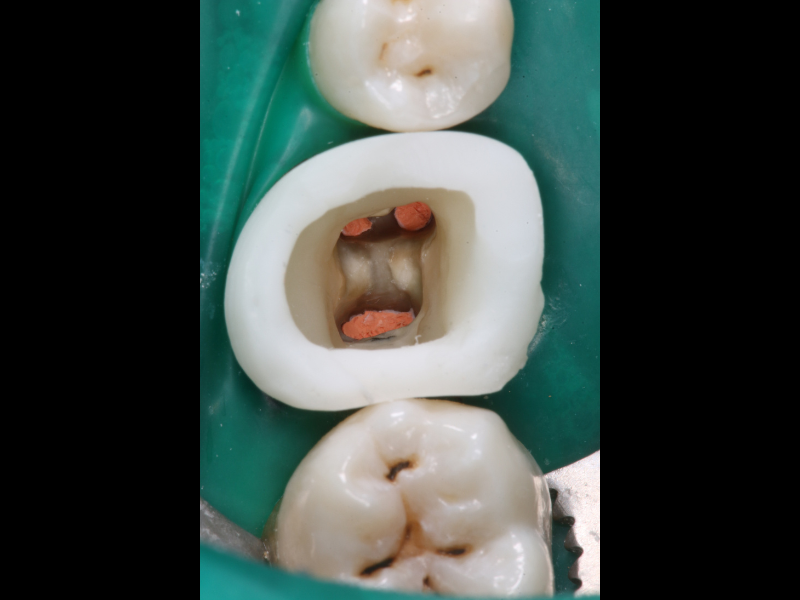

• Ridefinizione di una corretta cavità d’accesso

• Rimozione delle ritenzioni endocanalari: perni metallici e perni in fibra

• Rimozione dei materiali da otturazione canalare: confronto tra diverse tecniche